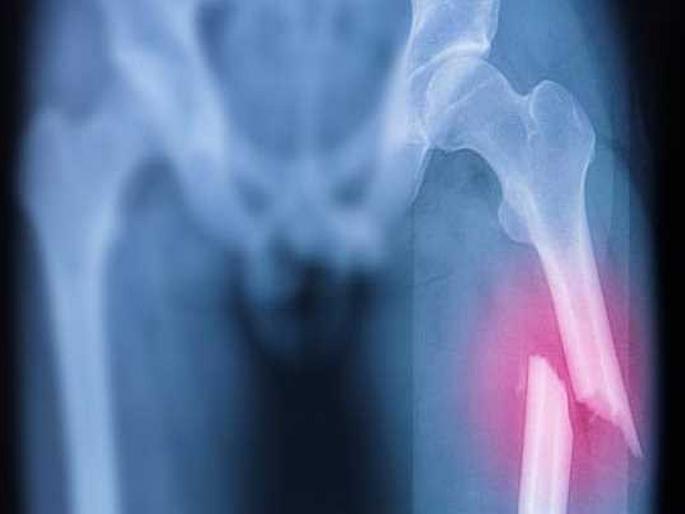

ऑस्टिओपोरोसिस म्हणजे हाडांसंबंधी एक असा आजार ज्यात हाडे कमजोर होतात. आणि यामुळेच हलक्या झटक्याने किंवा जखमेमुळे फ्रॅक्चर होण्याचा धोका अधिक वाढतो. इंटरनॅशनल ऑस्टिओपोरोसिस फाउंडेशनच्या अंदाजानुसार, दरवर्षी जगभरात साधारण २०० मिलियन महिला या आजाराच्या शिकार होतात. तर एका ताज्या रिसर्चनुसार, केवळ यूरोप, यूके आणि जपानमध्ये दरवर्षी साधारण ७५ मिलियन लोक ऑस्टिओपोरोसिसच्या समस्येशी लढत असतात. यात महिला आणि पुरूष दोघांचाही समावेश आहे.

इंटरनॅशनल ऑस्टिओपोरोसिस फाउंडेशनच्या अंदाजानुसार, दरवर्षी जगभरात ९ मिलियन फ्रॅक्चरचं कारण ऑस्टिओपोरोसिस आजार असतो. दरवर्षी साधारण २५ टक्के हिप फ्रॅक्टर याच आजारामुळे होतात. या आजाराने ग्रस्त असलेल्या पुरूषांमध्ये हिप फ्रॅक्चर मृत्यूचं मुख्य कारण आहे. ऑस्टिओपोरोसिसचे शिकार असलेल्या पुरूषांमध्ये हिप फ्रॅक्टरनंतर पहिल्या १२ महिन्यात मृत्यू दर जवळपास २० टक्के आहे.

(Image Credit : medicalnewstoday.com)